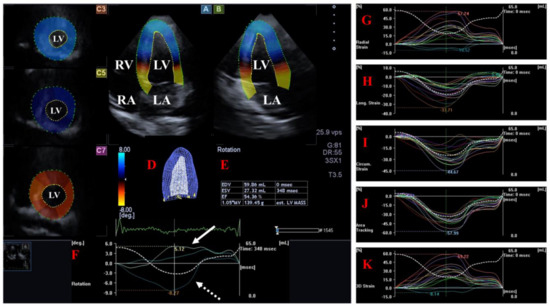

The LV is the central engine of systemic circulation. The two papillary muscles of the LV are required for the proper function of the mitral valve (MV) separating the LV and the left atrium (LA) and allowing blood flow from the LA into the LV during diastole. The blood leaves the LV via the aortic valve (AV), which prevents the backflow of blood from the aorta to the LV during diastole under healthy circumstances. The fibers in the subepicardium are left-handed, the mid-layer fibers run in the circumferential direction, while the fibers in the subendocardium are right-handed [16]. The LV moves in a 3D pattern including radial, circumferential and longitudinal deformation. This sort of movement can be characterized by several quantitative parameters named echocardiographic (unidirectional strains represented by its 3D motion: radial (LV-RS), longitudinal (LV-LS) and circumferential (LV-CS). While area (LV-AS) strain combines LS and CS, 3D (LV-3DS) strain combines all unidirectional strains [5,6,7,8,17,18,19,20]. In addition to the above, LV has a movement similar to wringing a towel called LV twist. In this case, the LV base rotates in a clockwise direction, while the LV apex rotates in a counterclockwise direction in systole [17,18,19] [Figure 1].

Figure 1.

Examination of the left ventricle (LV) by three-dimensional (3D) speckle-tracking echocardiography. Following echocardiographic data acquisitions, the following typical views are created: (A) Apical 4-chamber and (B) two-chamber longitudinal views and (C3,C5,C7) cross-sectional views at apical, midventricular and basal levels, respectively. LV can be easily detected alongside other heart cavities including the left atrium (LA) and the right atrium (RA) and ventricle (RV). A number of other details were also presented including (D) 3D cast and (E) end-diastolic (EDV) and end-systolic (ESV) volumes of the LV together with ejection fraction (EF) and mass of the LV and (F) curves representing changes in volumes and strains of LV over time. (F) Apical [white arrow] and basal [white dashed arrow] LV rotations and (G) radial, (H) longitudinal, (I) circumferential, (J) area and (K) 3D strains are also demonstrated.